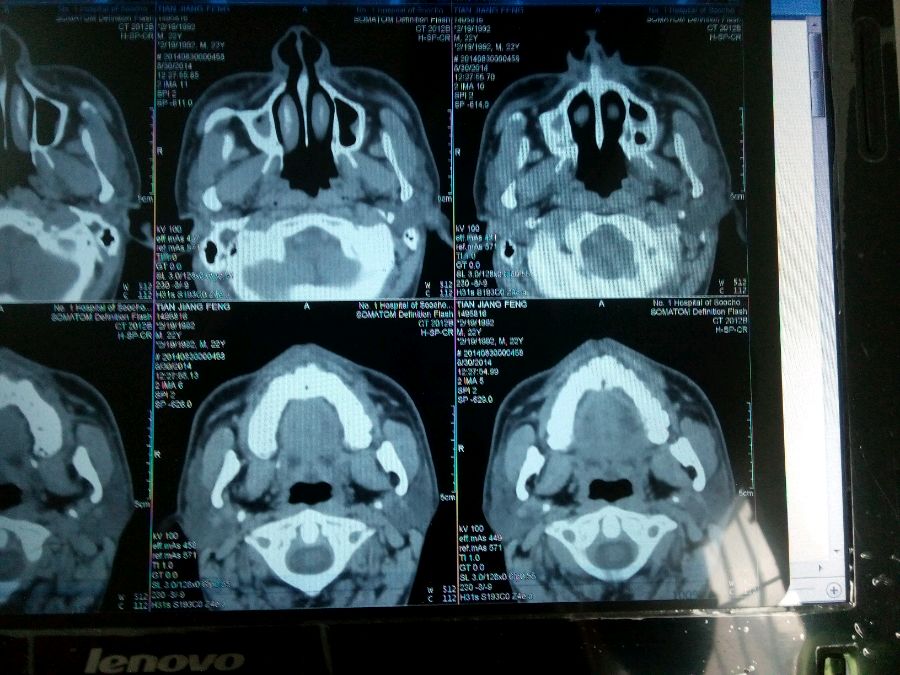

鼻骨骨折?? 鼻炎?鼻窦炎?请高人帮忙看看,谢谢了!

骨折看不清楚,右侧上颌窦积液(血?)

炎